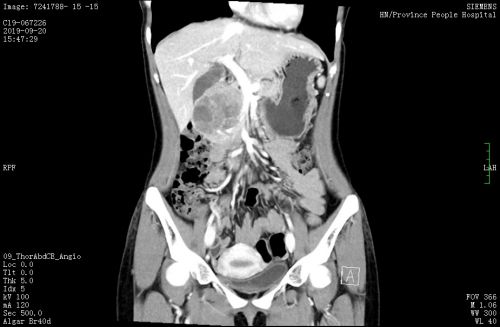

术前CT

22岁的小李来自湖南娄底,因发现胰头占位就医,医生建议行胰头十二指肠切除,但家属考虑患者年轻,这一手术需大范围切除患者的胰头、十二指肠、胃窦、胆囊、肝外胆管和一部分空肠,担心术后生理功能受到影响。经人介绍找到捷克论坛肝脏外二科主任毛先海教授,入院后完善相关检查,肿瘤标志物均阴性,CT及核磁共振考虑胰头病变,实性-假乳头肿瘤可能性大。考虑患者为良性病变,毛先海教授表示,可以考虑选择保留功能的胰腺术式,术后不会影响生理功能,并且可以采用腹腔镜完成手术。听说不会在腹部留下“蜈蚣”样的手术疤痕并且可以尽量保留自己正常的生理功能,小李当即要求毛教授为自己手术。